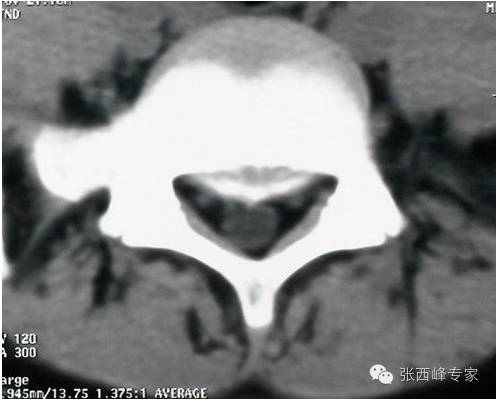

CT腰5骶1椎间盘突出

水平位腰5骶1椎间盘突出